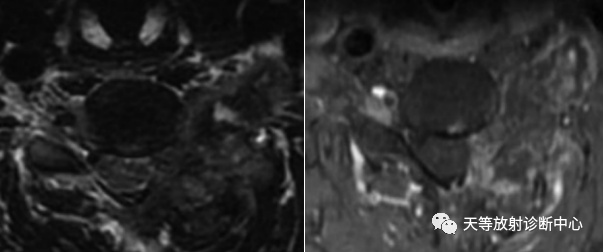

男性,54岁。男性,54岁。

椎体骨质破坏并见大量软骨基质形成

软组织窗骨质破坏呈溶骨性、外生性生长,内部见大量钙化影。

骨质破坏呈溶骨性,大量钙化,肿块向外生长,局部突入椎管内。

病例1:上图:软骨肉瘤。CT显示椎管及其附件骨质溶骨性破坏,椎体周围软组织肿块并含大量钙化影,钙化呈斑片状、斑点状不定型。整个肿块外生性生长为主,局部突入椎管内。

上图:同一病例,MRI显示肿块内信号混杂,T1WI以低信号为主含少量高信号影。增强扫描病灶内呈斑片状强化。